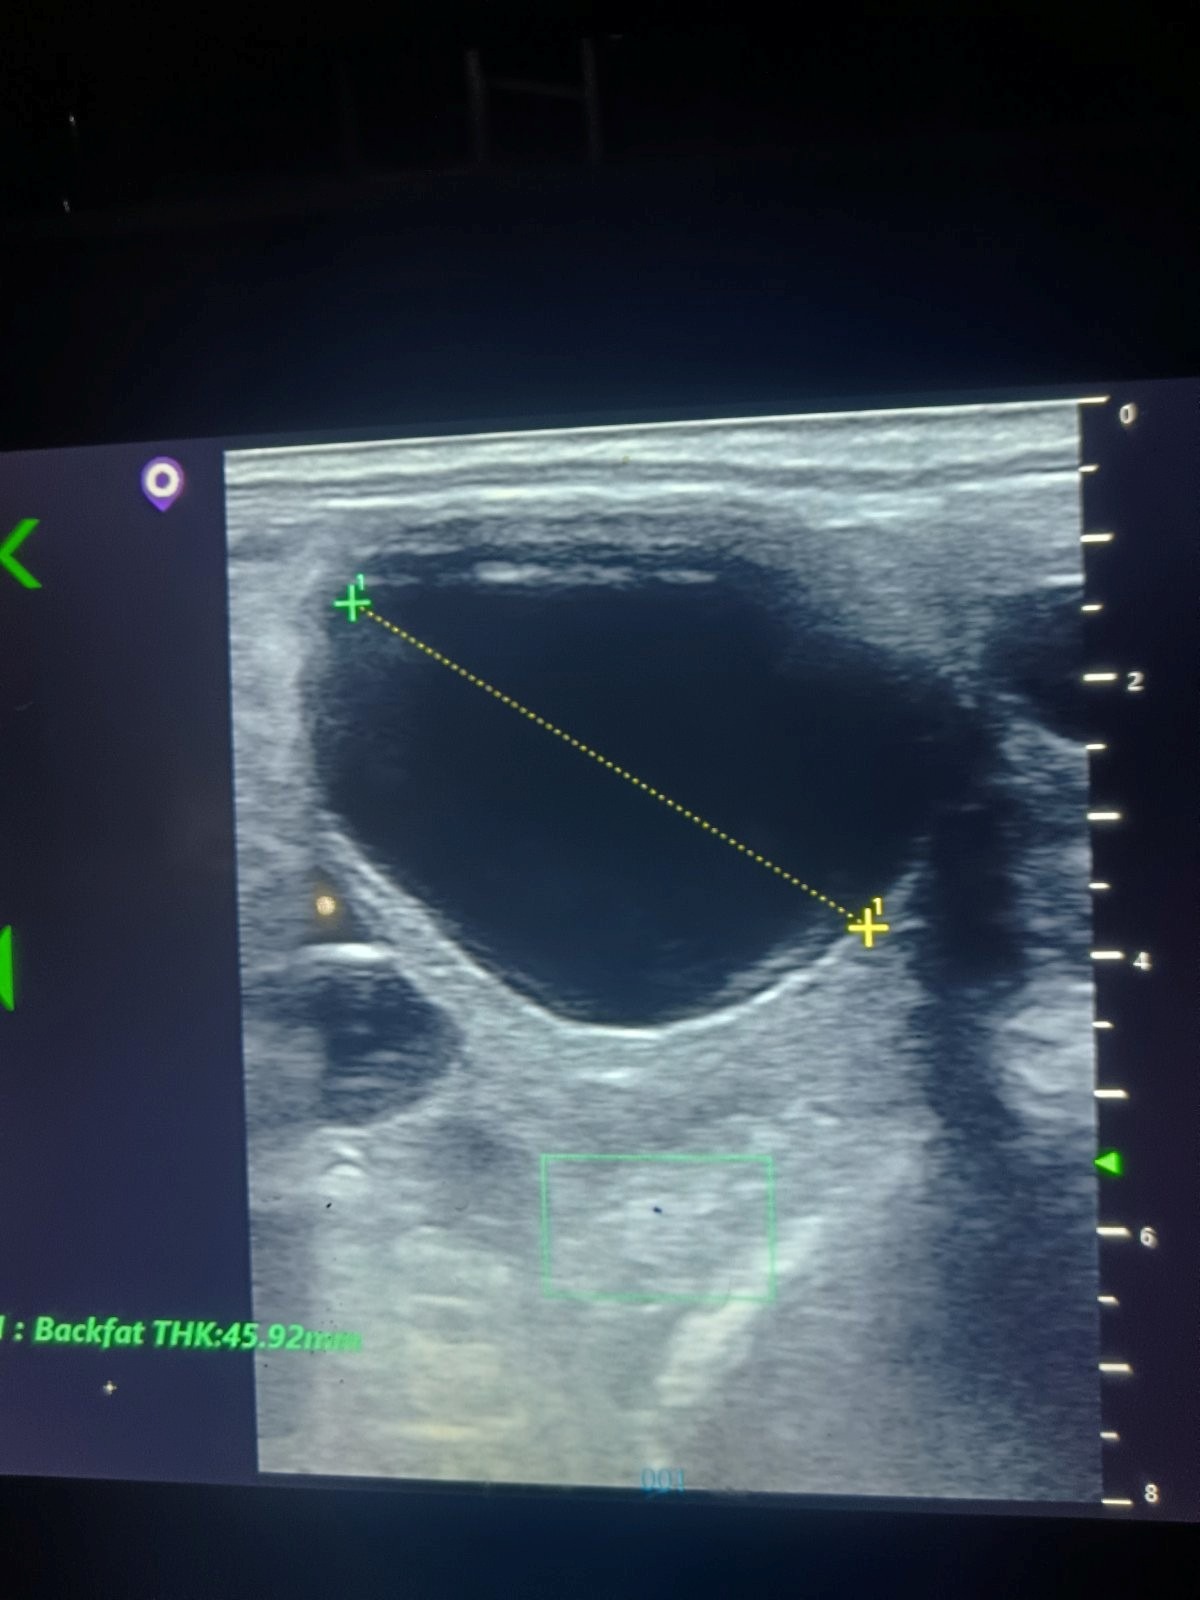

Osemenjavanje kobila sa svežim ili zamrznutim semenom, kao i kontrola uspeha nakon osemenjavanja sprovodimo sa kolor-dopler ultrazvučnom dijagnostikom. Ovom tehnikom jasnije se očitava aktivnost krvnih sudova pre ovulacije kao i rad srca ploda u ranim fazama razvoja.

Zbog specifičnosti estralnog ciklusa kobila (produžene ovulacije) i skupih semena, neophodno je pratiti rast folikula unutar nekoliko dana sve do momenta neposredno pred ovulaciju, kada se sprovodi osemenjavanje. Više o tome: